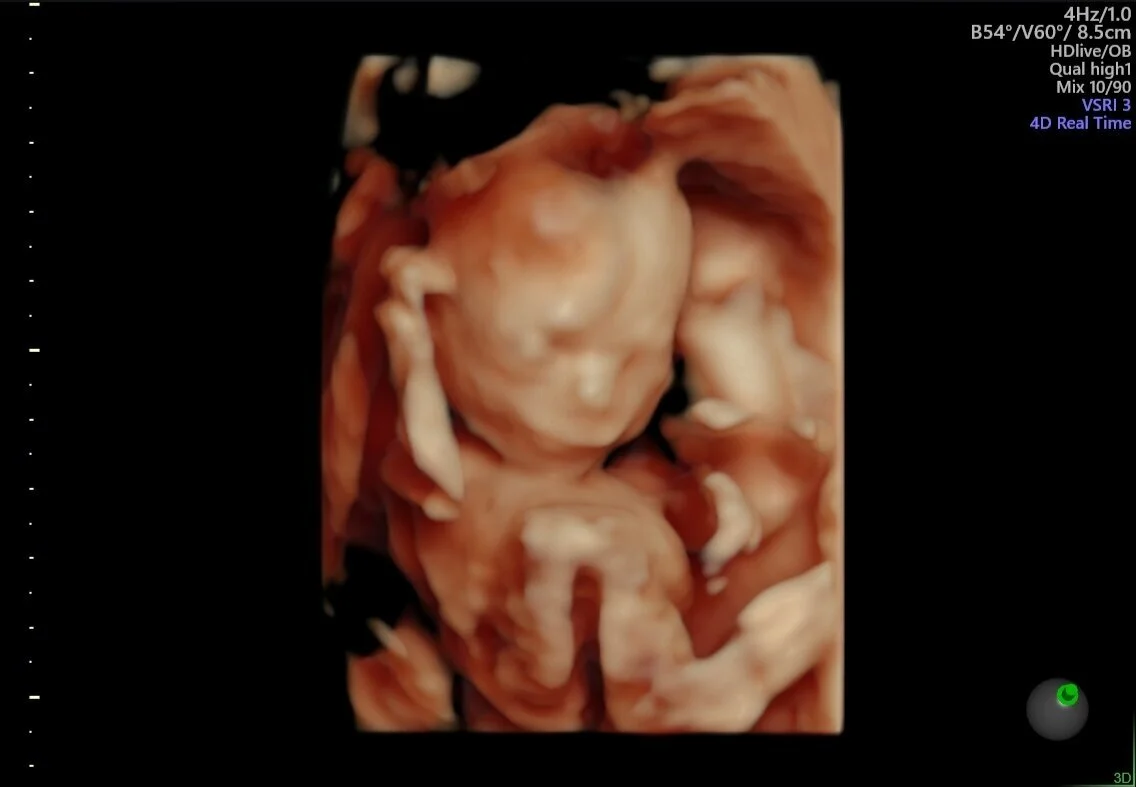

Obstetra Faz Sucesso Ao Comparar Ultrassom 3d E Fotos De Bebes Apos Nascimento

Medico Prova Que E Possivel Ver Exatamente O Rosto Do Bebe Com O Ultrassom 4d Familia

Fotos De Bebes Antes E Depois Do Nascimento Sao A Coisa Mais Fofa